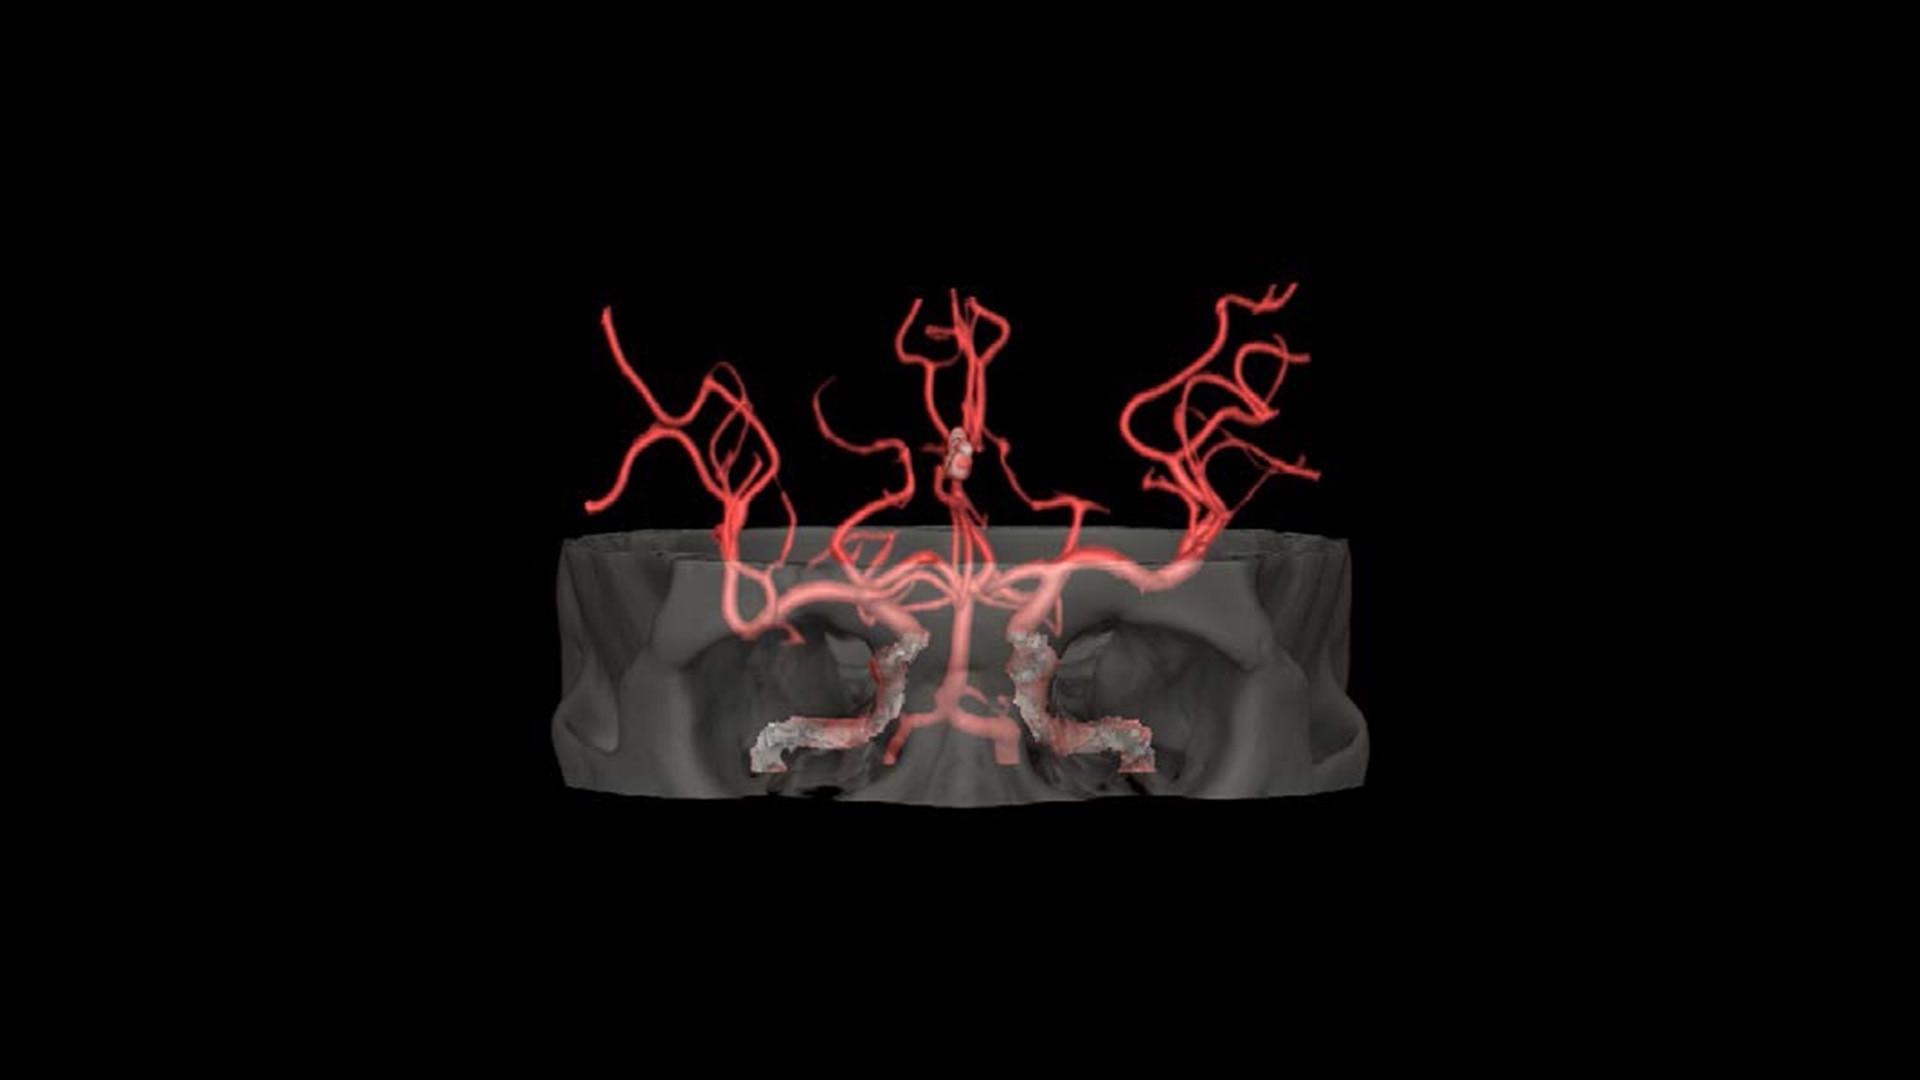

Advanced Visualization

Elevate your CT imaging with our collection of advanced visualization applications that assist reading, automate post-processing and streamline imaging review.